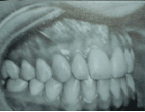

Relacione a coluna da direita com a da esquerda, conforme os problemas encontrados nas fotografias intraorais e depois marque a sequência correta.

(1) Retrator muito pequeno

(2) Fotografia tomada abaixo do plano oclusal

(3) Retrator muito grande e muito visível

(4) Fotografia não tomada para o lado suficiente

(5) Fotografia tomada acima do plano oclusal

( )